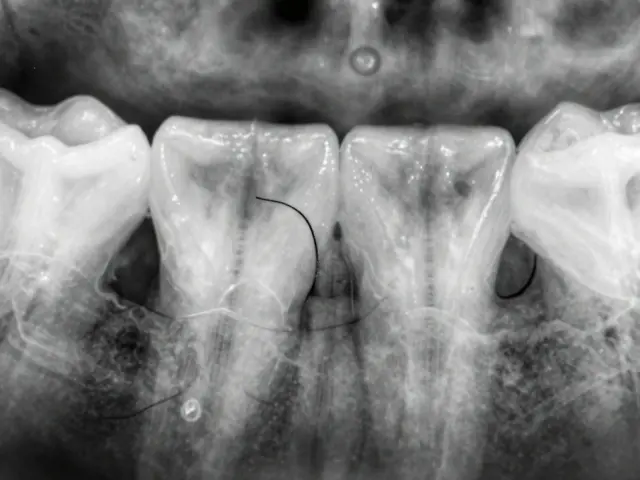

Důležité je zmínit, že výběr implantátu a jeho velikost se liší podle individuálních potřeb pacienta, což zahrnuje stav čelisti, množství kosti a zdraví dásní. Před samotným zákrokem se provádí důkladné vyšetření a plánování prostřednictvím rentgenů a, v některých případech, 3D scannerů.

Zavedení zubního implantátu je komplexní proces, který začíná důkladnou konzultací s odborníkem na stomatologii. Nejprve je nutné zhodnotit celkový zdravotní stav pacienta, aby bylo jisté, že je vhodným kandidátem na tento zákrok. To zahrnuje detailní anamnézu, rentgenové snímky a v některých případech i 3D skenování čelistí.